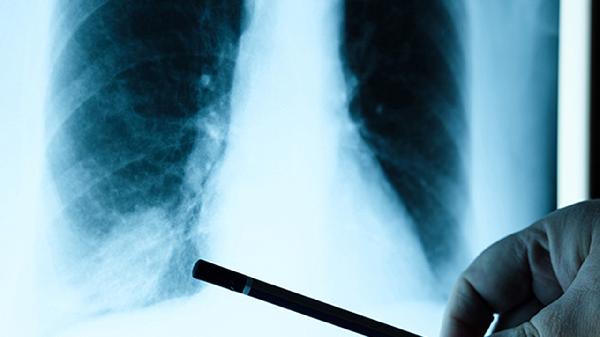

肺片状高密度影的原因是什么

肺片状高密度影可能由肺炎、肺结核、肺水肿、肺栓塞、肺肿瘤等原因引起。肺片状高密度影通常表现为咳嗽、胸痛、呼吸困难等症状,需结合影像学检查及临床表现综合判断。